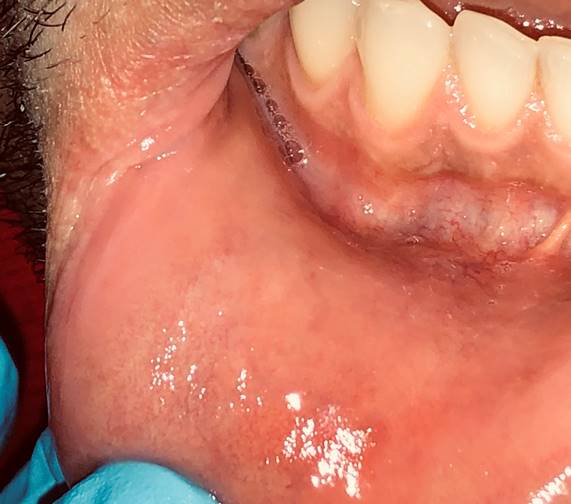

Dry and cracked lower lip vermilion border was observed during the clinical examination. A 3 x 4 cm ulcer appears at the lower right lip mucosa. It has very hardened edges associated with erosive areas. The base is covered with a yellowish pseudomembrane that is painful to palpation and when brushing against the teeth. The patient reports a smaller lesion at first, which he thought was a bite or injury. But the lesion did not heal and instead grew in two months (Fig. 1A). He had two enlarged lymph nodes measuring 2 cm on the neck, on the right level III. They were ovoid and painful on palpation, with an evolution of two days. No facial or skin contour alterations were observed (Fig. 1B).

Fig. 1: A. Ulcer on the right lower lip mucosa, 3 x 4 cm, hardened edges associated with erosive areas and the base covered with yellowish pseudomembrane. B. Two 2 cm enlarged lymph nodes, ovoid in shape, at level III of the right side of the neck